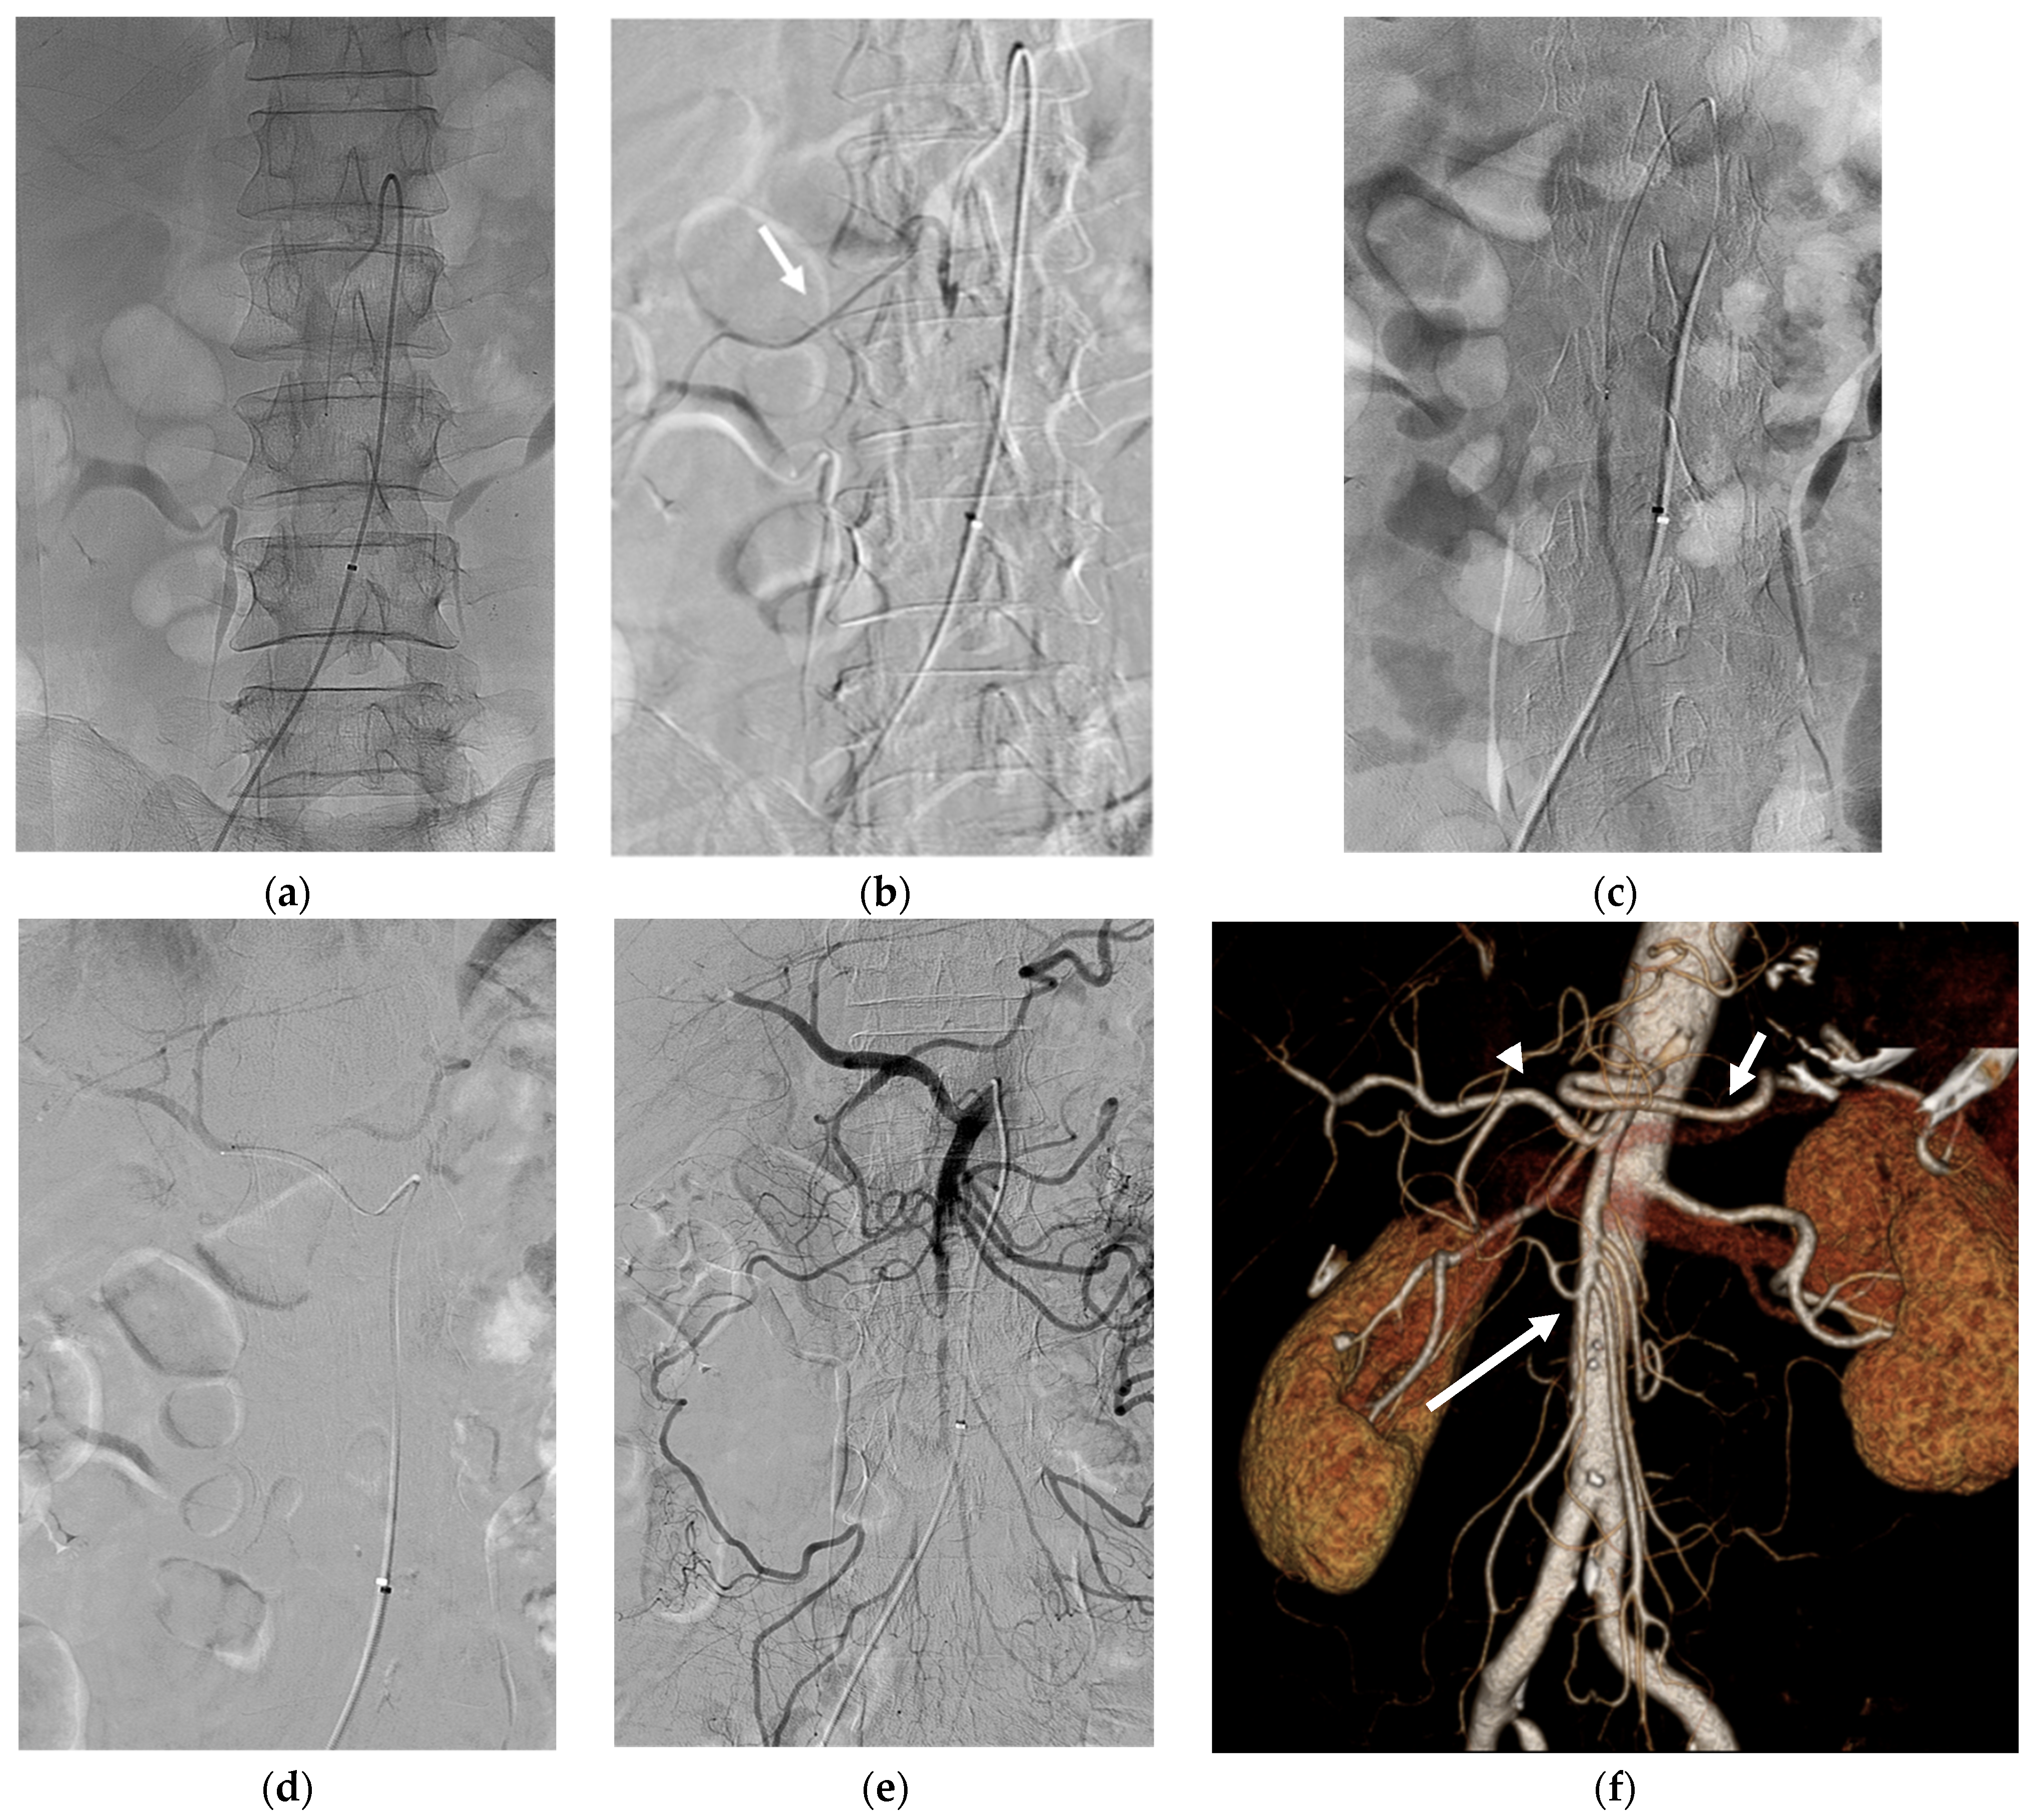

Figure 3. (a) The 1.9Fr microcatheter was advanced in front of the SMA occlusion site and 0.5 mg of rtPA was injected for 10 min. (b) After the injection, angiography revealed partial recanalization of right colic flow (arrow). (c) The microcatheter was then advanced into the middle and distal SMA and 0.5 mg of rtPA was injected for 10 min. (d) The CHA was also selectively catheterized using the microcatheter and 0.5 mg of rtPA was injected for 10 min. (e) Final angiography revealed near total recanalization of SMA and its branches. (f) After 2 days, follow-up three-dimensional volume-rendered image of abdominal CT angiography revealed successful recanalization of the SMA (long arrow), the CHA (arrowhead), and the splenic artery (short arrow).

A 1.9 Fr microcatheter was advanced immediately in front of the SMA occlusion site, and 0.5 mg of rtPA (5 mL solution) was injected for 10 min. After the injection, angiography revealed partial recanalization of right colic flow. The microcatheter was then advanced into the middle and distal branches of the SMA, and rtPA (0.5 mg) was injected again for 10 min. Additionally, the CHA and splenic artery were selectively catheterized using a 5 Fr RH catheter and a microcatheter. Subsequently, 0.5 mg of rtPA was injected into each artery in front of the occluded site. The final angiogram revealed near-complete revascularization of the SMA (Figure 3). To avoid bleeding complications, no additional rtPA was administered.

After the procedure, the patient was admitted to the intensive care unit and was administered continuous intravenous heparin infusion. No immediate major or minor postoperative complications occurred. After two days, contrast-enhanced CT revealed successful recanalization of the SMA and CHA occlusion without bowel ischemia or active bleeding. Eight days after thrombolysis, the patient was discharged and subsequently treated with warfarin for atrial fibrillation.